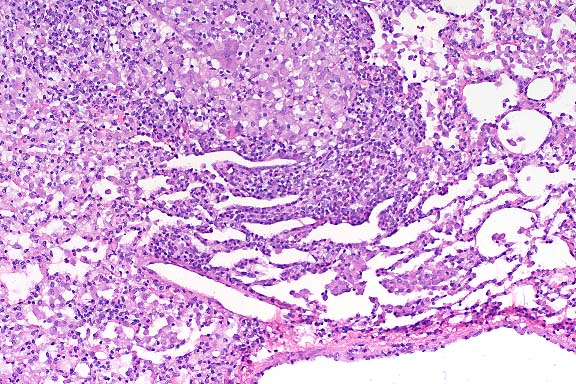

The specimen consists of skin and subjacent thigh muscle. Focal ulceration with severe neutrophilic inflammation is present in the epidermis. There is widespread suppurative inflammation, granulation tissue and coagulation necrosis in the muscle. Individual myofibers are swollen, hyalinized, and fragmented. Marked numbers of neutrophils surround myofibers undergoing myocytolysis and mineralization.

Conference Note: Adjacent to ulcerated areas in some sections there are moderate numbers of mixed bacteria.

With intramuscular injection, gross lesions vary depending on the dose administered and the numbers of days post-injection. In rats and hamsters at one day post-injection (DPI), subcutaneous and fascial hemorrhage, edema, and brownish discoloration of the tissue are found. At 3 DPI, pale white areas in the muscle with ulcers over the injection site are observed. Lesions become more severe with higher doses. Histologically, there is a central area of muscle necrosis characterized by sarcoplasmic swelling, hyalinization of muscle fibers, loss of striations, fragmentation, and centralized or faded nuclei. At 24 hours post-injection, a zone of inflammatory cells composed primarily of neutrophils surrounds necrotic muscle, while at three to seven days, lymphocytes, macrophages, and fibroblasts predominate. At 14 DPI, fibrous connective tissue and small foci of mineralization replace large bands of muscle.